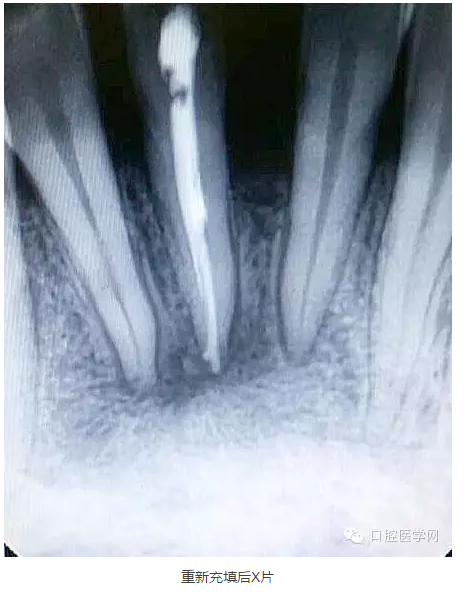

下面是一例 今年年初治療的下前牙根尖囊腫病例,患者因故未能按時(shí)復(fù)診,最近才來(lái)。